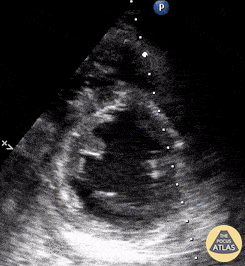

Seen here is a parasternal short-axis view from a patient who presented with sepsis. POCUS was notable for sepsis-induced cardiomyopathy. Johannes Achenbach